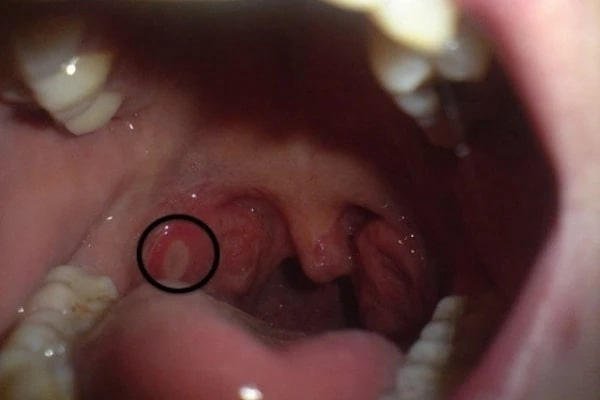

Nhiệt miệng ở cổ họng

Trẻ bị nhiệt miệng ở họng khi bị chấn thương hoặc mắc các bệnh lý. Trẻ sẽ cảm thấy đau, khó nuốt, buồn nôn, miệng có mùi hôi,… Những vết nhiệt này thường gây phá hủy lớp niêm mạc lót ở họng, tạo ra vết thương hở khó lành.